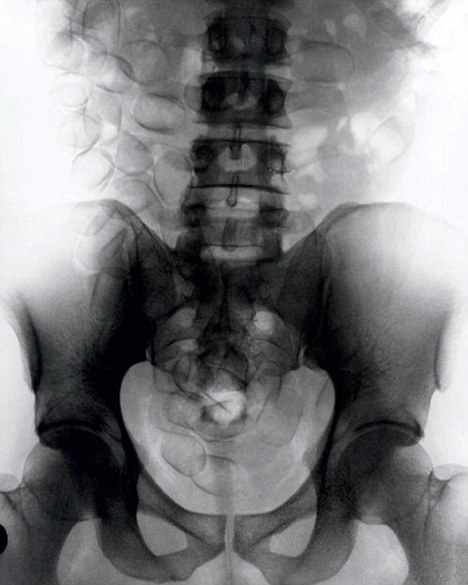

現(xiàn)年30歲的菲達(dá)利斯(Fidelis Ozouli)冒著生命危險(xiǎn)將重達(dá)1公斤的毒品吞下,被抓后卻辯稱不知道吞下的是毒品。當(dāng)時(shí),曼徹斯特機(jī)場(chǎng)的海關(guān)人員看到毒販菲達(dá)利斯臃腫的肚腩,顯得很不自然,于是開(kāi)始懷疑。檢查人員用X射線機(jī)照他的胃部時(shí),發(fā)現(xiàn)了大量可卡因。目前他已被送往附近醫(yī)院,以確保排出所有的毒品。

這名男子還將毒品藏在幾十個(gè)避孕套里,估計(jì)純度為78%,價(jià)值25萬(wàn)英鎊。毒販后來(lái)被帶到曼徹斯特皇家法庭,自稱來(lái)自尼日利亞,目前在倫敦生活和學(xué)習(xí)。他承認(rèn)攜帶A類(lèi)毒品入關(guān)確實(shí)犯了法,但否認(rèn)他吞下的是毒品。目前他已經(jīng)被英國(guó)警方正式逮捕,案件已轉(zhuǎn)交給毒品稽查部門(mén),預(yù)計(jì)他將被判入獄10年。